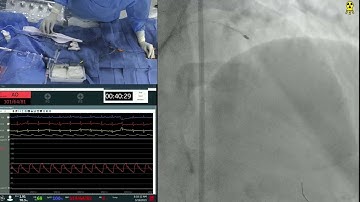

LAD-D2 Bifurcation Lesion PCI using 2-Stent Technique - CCC Live Oct 2016